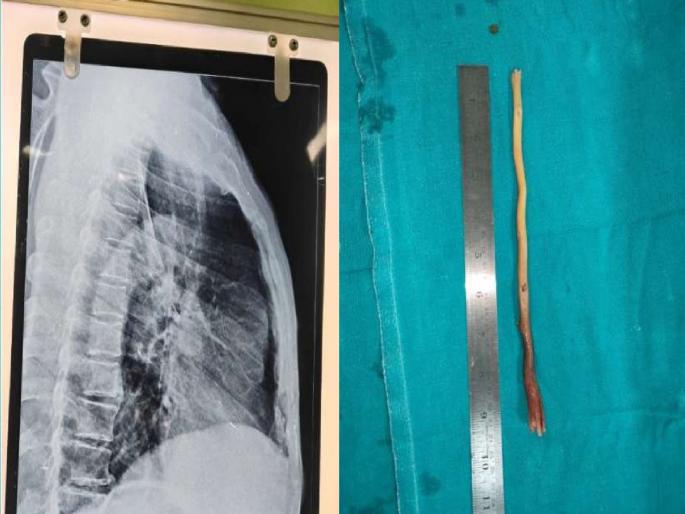

९ डॉक्टरांच्या टीमने 'एसोफॅगोस्कोपी' नावाची तंत्राचा वापर केला. या प्रक्रियेत घशात एक विशेष नळी टाकली जाते, ज्याद्वारे आतल्या गोष्टी पाहता काढता येतात. या नळीद्वारे हळूहळू दाब देऊन काडी बाहेर काढण्यात आली. ऑपरेशन पूर्णपणे यशस्वी झाल्यानंतर हळुहळू कामराजू नायक यांची प्रकृती सुधारली.

अनेक वैद्यकीय केंद्रांमध्ये दाखवल्यानंतर कामराजूंच्या कुटुंबीयांनी त्यांना ब्रह्मपूर येथील एमकेसीजी मेडिकल कॉलेजमध्ये नेले. येथे ईएनटी विभागाचे डॉ. संजीत कुमार मिश्रा आणि त्यांच्या टीमने ताबडतोब त्यांची तपासणी केली. तपासणीत असे दिसून आले की, काडीचा तुकडा अन्ननलिकेत अडकला होता. कामराजू यांच्या वृद्धापकाळामुळे शस्त्रक्रिया धोकादायक होती. त्यांना उच्च रक्तदाब आणि इतर अनेक आरोग्य समस्या होत्या. अशा परिस्थितीत डॉक्टरांनी उपचारांचे नियोजन अतिशय काळजीपूर्वक केले.